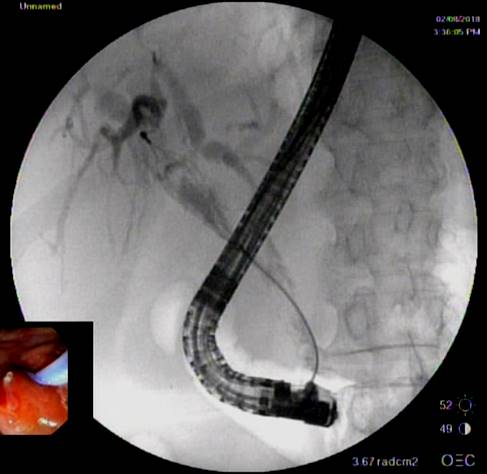

Представлены клинические наблюдения редкого осложнения эхинококкоза печени – прорыва эхинококковой кисты в желчные протоки. Осложнение стало причиной обструкции желчных протоков, механической желтухи и холангита. Освещены этапы диагностики, роль УЗИ в выявлении осложнений эхинококкоза печени, рассмотрены способы минимально инвазивного лечения с применением эндоскопических и чрескожных технологий под контролем лучевых методов.